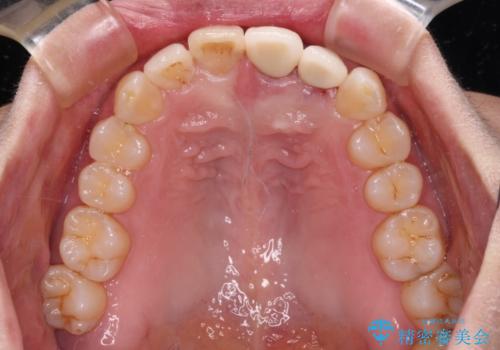

- 下顎前歯が抜けそうとのことで来院された患者様です。

初診の状態ではすぐにでも抜けそうな状態で、インプラントによる補綴治療を行うこととしました。

インプラント治療に際し、前歯の叢生に対する矯正治療を提案したところ、興味を持たれたので、インビザライン・ライトによる矯正治療を行うこととしました。

抜歯後にスペースができると恥ずかしいため、抜歯した歯を接着剤で固定した上で矯正治療を行い、その後インプラントやオールセラミッククラウンの装着を行うこととしました。